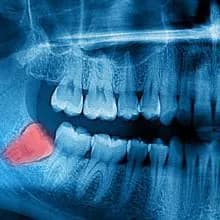

01. DIAGNÓSTICO

Evaluamos la complejidad del caso con examen clínico y radiografía panorámica 2D (el mismo día). Según la severidad, podemos solicitar un TAC 3D.